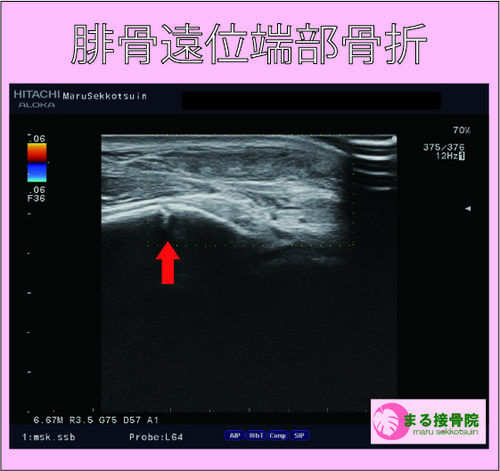

受傷直後から見る見ると足首の外くるぶしが腫れてきたとのことで、下の写真は受傷後30分くらい経過した時のものです。

結果、外くるぶしの骨折「腓骨遠位端部骨折」でした。

外くるぶしの骨折は、足首を内返しに捻挫した時に、たまに起こる骨折でして、子供から大人まで起こりうる骨折です。